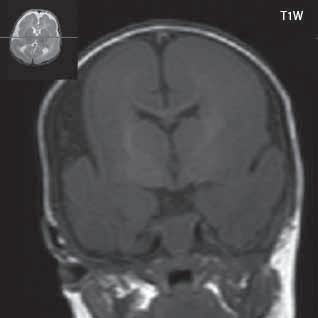

Obr. I.1.1h Fyziologický nález, již normální šíře subarachnoidálních prostor (věk 1,5 roku); stejný pacient jako na obr I 1 1f, g

Obr. I.1.1ch Fyziologický nález, již normální šíře subarachnoidálních prostor (věk 1,5 roku); stejný pacient jako na obr I 1 1f, g, h